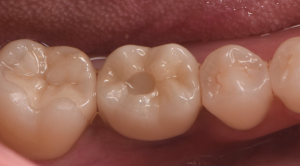

根が折れた奥歯をインプラントで治療した症例

右下の奥歯が噛むと痛むとのことでご来院されました。太い金属の土台によって根に大きな負担がかかり、かぶせものの下で縦に割れてしまっていることがわかりました。残念ですが歯が割れてしまうと残すことはできませ…